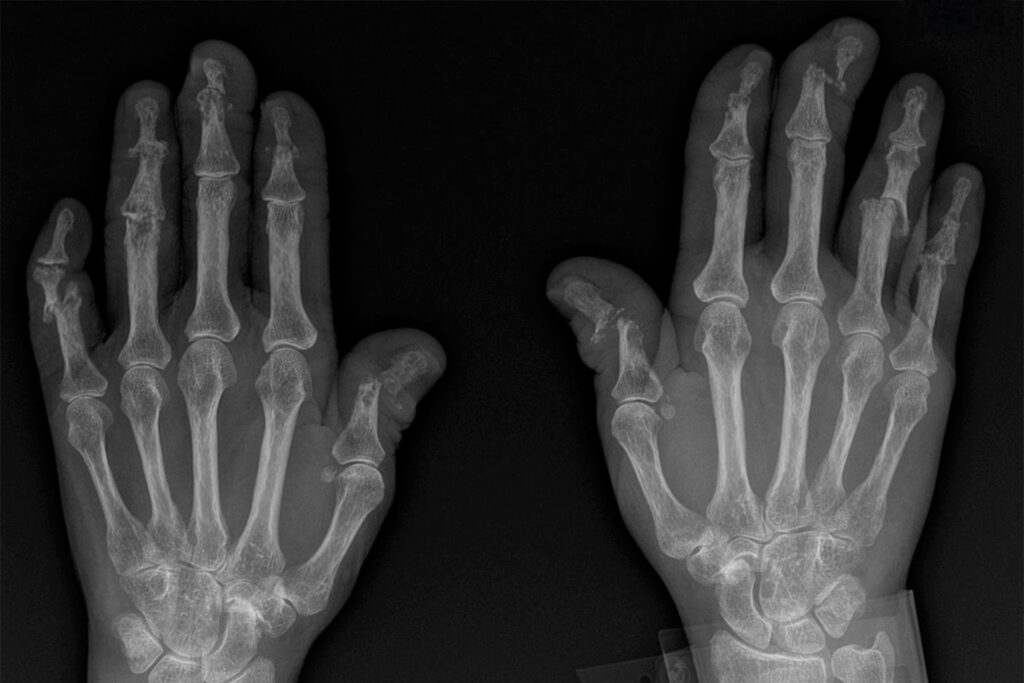

En radiolog eller reumatolog leder efter specifikke forandringer, der tilsammen tegner et billede af psoriasisgigt. Disse fund er ofte asymmetriske, hvilket betyder, at de ikke nødvendigvis rammer de samme led på begge sider af kroppen.

I modsætning til leddegigt, hvor fokus primært er på knoglenedbrydning, ses der ved psoriasisgigt en kamp mellem nedbrydning og opbygning. Røntgenbilledet kan vise:

- Marginale erosioner: Små 'bid' i kanten af knoglen inde i leddet.

- Periostitis: Inflammation af knoglehinden (periosteum), som får kroppen til at danne nyt knoglevæv. Dette kan give knoglen et 'flosset' eller 'uldent' udseende på røntgenbilledet. I nogle tilfælde kan en hel finger- eller tåknogle blive 'indkapslet' i nyt knoglevæv.

- Enthesopati: Betændelse der, hvor sener og ledbånd hæfter på knoglen (entheser). Dette kan føre til både erosion og knoglenydannelse på disse specifikke steder, hvilket ofte ses som små knogleudvækster.

"Blyant-i-kop" Deformitet

Dette er måske det mest klassiske og velkendte røntgenfund ved psoriasisgigt, selvom det ikke er til stede hos alle. Blyant-i-kop (pencil-in-cup) beskriver en alvorlig form for erosion, hvor den ene knogleende i et led (ofte i hænder eller fødder) eroderes, så den bliver spids som en blyant. Samtidig udvides og udhules den modstående ledflade, så den danner en form som en kop, som 'blyanten' passer ind i. Dette er et tegn på fremskreden sygdom.

Dactylitis ("Pølsefinger" eller "Pølsetå")

Et meget karakteristisk klinisk tegn er dactylitis, hvor en hel finger eller tå hæver op og kommer til at ligne en lille pølse. På et røntgenbillede kan man se, at denne hævelse skyldes en kombination af ledinflammation (synovitis) og seneskedehindebetændelse (tenosynovitis), ledsaget af bløddelshævelse.

Andre vigtige fund i hænder og fødder

- Acro-osteolyse: Dette er en proces, hvor de yderste knogler i fingre og tæer (terminale falanger) gradvist opløses. Dette kan ses som en afkortning af fingerspidserne.

- Ankylose: I nogle tilfælde kan inflammationen blive så alvorlig, at knoglerne i et led vokser sammen. Denne proces, kendt som ankylose, fører til et fuldstændigt stift led uden bevægelighed. Det ses oftere i de små led i hænder og fødder ved psoriasisgigt end ved leddegigt.

- Elfenbensfalanks (Ivory Phalanx): Et sjældnere, men karakteristisk tegn, hvor en knogle i en tå (ofte storetåens yderste knogle) bliver unormalt tæt og hvid på røntgenbilledet, hvilket minder om elfenben.